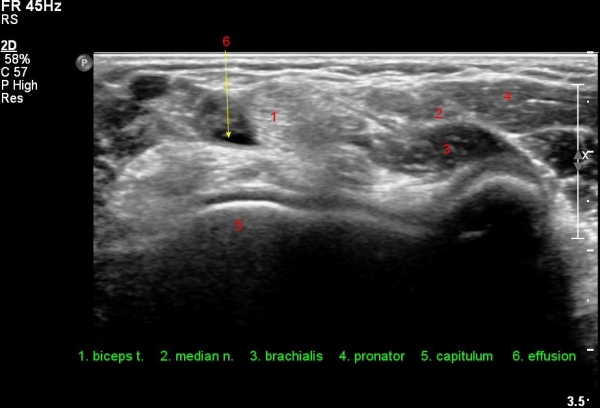

ÀÌµÎ¹Ú±Ù°Ç Á¾´Ü¸é°Ë»ç¿¡¼­ ¿ä°ñµ¹±âÀÇ µ¹Ãâ°ú °ñ±ØÀÌ °üÂûµÇ°í À̵θ·±Ù°ÇÀº Àú¿¡ÄÚ ºÎÁ¾°ú ¿¬°á ¼Ò½ÇÀÌ °üÂûµÊ(»çÁø 4, 5).

Àü¿ÏÀ» ȸ³»ÇÑ »óÅ¿¡¼­ ÆÈ²ÞÄ¡ µÚÂÊ¿¡¼­ ¿ä°ñµ¹±âÀÇ µ¹Ãâ°ú ÀÌµÎ¹Ú±Ù°Ç ºÎÂøºÎÀÇ Àú¿¡ÄÚ ºÎÁ¾ÀÌ °üÂûµÊ(»çÁø 6).